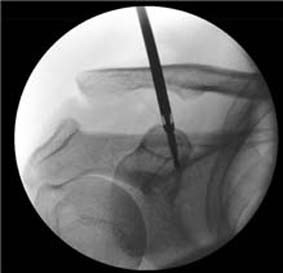

Á¤Çü¿Ü°ú ¼ö¼ú °ü·Ã ±¹Á¦ÇмúÁöÀÎ 'International Journal of Advanced Research'¿¡ ¹ßÇ¥µÈ À̹ø ³í¹®Àº ¡®Comparison between Hook Plate Fixation with and without Additional Anchor Fixation for Acute Acromioclavicular Joint Dislocations¡¯¶ó´Â Á¦¸ñÀ¸·Î ¾î±ú °ß¼â°üÀý ¼Õ»ó Ä¡·á¹ý¿¡ °üÇÑ ³í¹®ÀÌ´Ù.

| | ¡è¡è ¡ã ºÀÇÕ³ª»ç¸¦ ÀÌ¿ëÇÑ °ß¼â Å»±¸ÀÇ Hybrid °íÁ¤¼ú <»çÁøÁ¦°ø=õ¾È¾Æ»êÃæ¹«º´¿ø> | ¨Ï ¿Â¾ç½Å¹® | À¯À缺 ±³¼ö°¡ ¹ßÇ¥ÇÑ À̹ø ¿¬±¸ °á°ú¿¡ µû¸£¸é ¾î±ú °ß¼â °üÀý Å»±¸ ¹× ¼Õ»ó ȯÀÚ¿¡°Ô °í½ÄÀûÀÎ °¥°í¸® ±Ý¼ÓÆÇ °íÁ¤¹ý ½ÃÇà ½Ã Ãß°¡ÀûÀ¸·Î ºÀÇÕ³ª»ç °íÁ¤À» ½ÃÇàÇÔÀ¸·Î½á, ±Ý¼ÓÆÇÀ» Á¦°ÅÇϱâ±îÁöÀÇ Ä¡·á±â°£À» ´ÜÃà½Ã۰í, ºó¹øÇÏ°Ô ¹ß»ýÇÏ´Â °¥°í¸® °ü·Ã ÇÕº´Áõ ¹× Á¤º¹ ¼Ò½ÇÀ» ÃÖ¼ÒȽÃŰ´Â °á°ú¸¦ ³Â´Ù´Â Á¡¿¡¼ ÀÇ¹Ì ÀÖ´Â ¿¬±¸·Î Æò°¡ ¹Þ¾Ò´Ù.

| | ¡è¡è ¡ãºÀÇÕ³ª»ç ÇÏÀ̺긮µå °íÁ¤ ½Ã Ä¡·á±â°£ ´ÜÃà ¹× ÇÕº´Áõ °¨¼ÒÀÇ °á°ú¸¦ ³ªÅ¸³Â´Ù <ÀÚ·áÁ¦°ø=õ¾È¾Æ»êÃæ¹«º´¿ø> | ¨Ï ¿Â¾ç½Å¹® | |